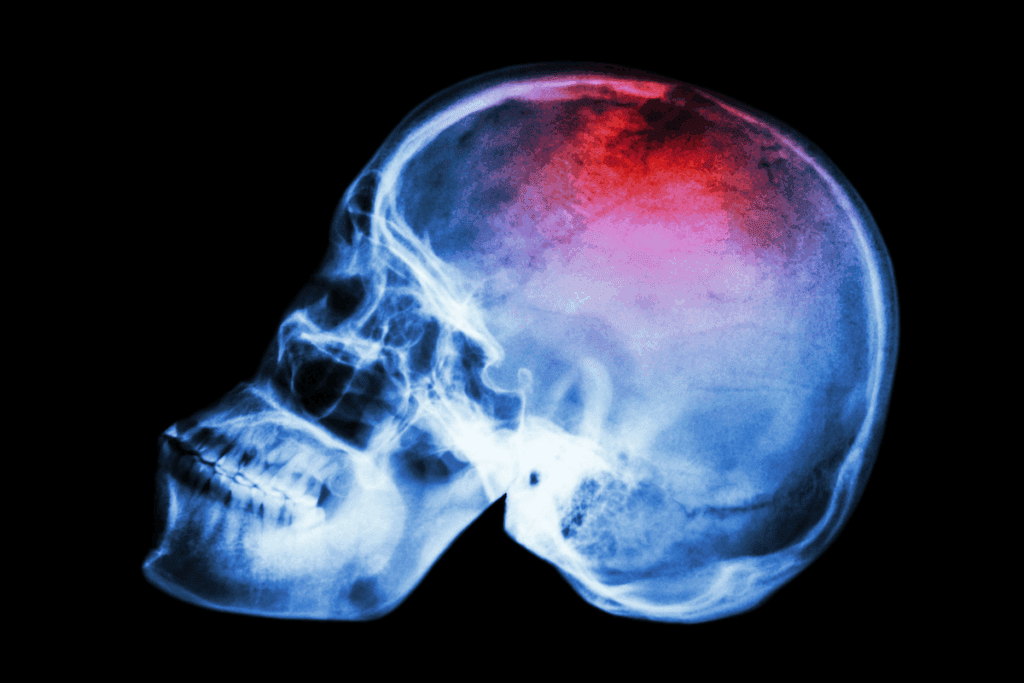

Imaging Studies

Imaging studies are vital for diagnosing skull osteosarcoma. They show how big and where the tumor is. Common tools include:

- Radiographs (X-rays): Show the bone’s structure and any issues.

- Magnetic Resonance Imaging (MRI): Gives detailed views of soft tissues and tumor size.

- Computed Tomography (CT) scans: Check bone damage and tumor calcification.